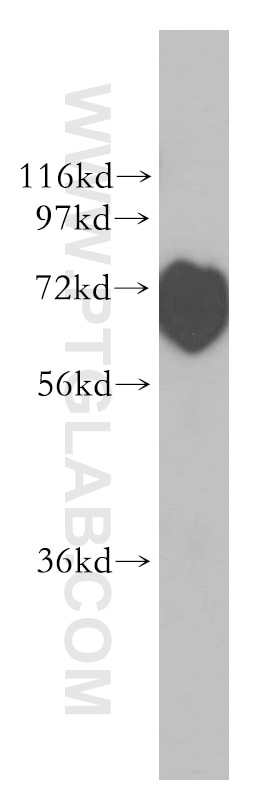

| Positive WB detected in | rat kidney tissue |

| Calculated Molecular Weight | 383 aa, 42 kDa |

| Observed Molecular Weight | 42 kDa |

NPHS2 (also known as Podocin) is a membrane protein located on the podocyte foot process and is the critical component of the glomerular filtration barrier. Mutations of NPHS2 cause recessive steroidresistant nephrotic syndrome. Two isoforms of NPHS2 exist with molecular weights of 42 kDa and 35 kDa, respectively. (PMID: 21499232)